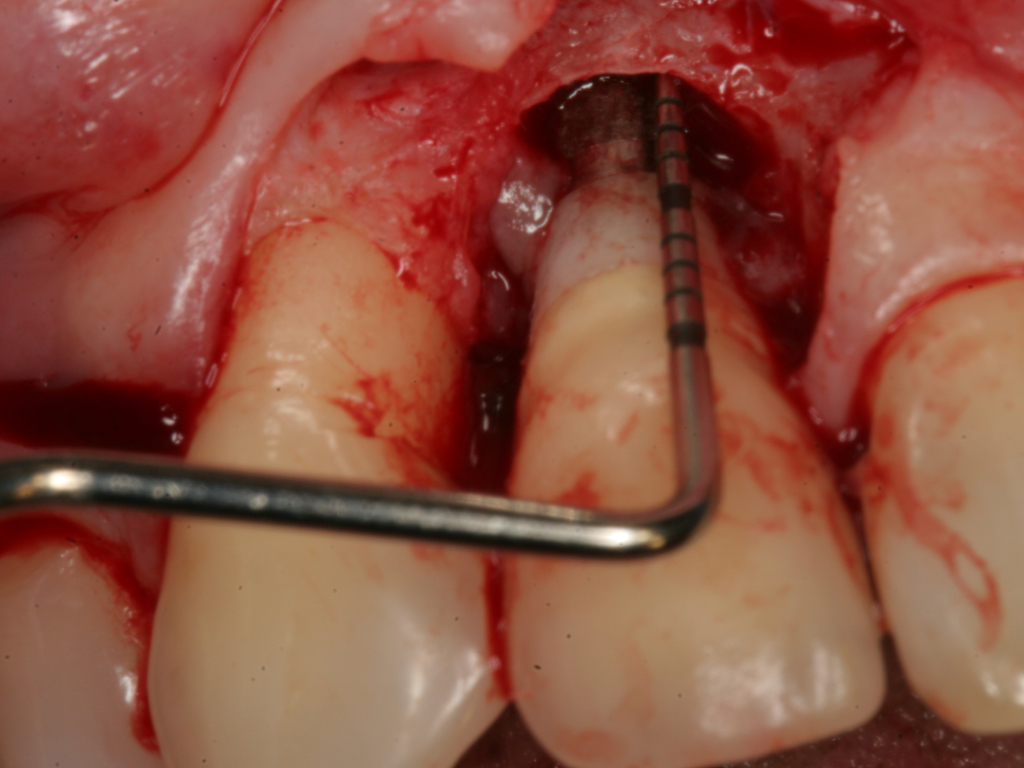

Probing is useful to determine the presence of biological complications at the buccal and lingual sites of implants, which cannot be evaluated on a radiograph (Figure 6 through Figure 8). Because of the absence of a periodontal ligament, bone loss on the buccal and lingual aspects of an implant indicates loss of support for the implant and may be a sign of additional circumferential bone loss around the implant.35

Fig 7. Probing of the buccal surface reveals additional loss of attachment around the dental implant.

Figure 7

Fig 8. Flap elevation confirms circumferential bone loss.

Figure 8